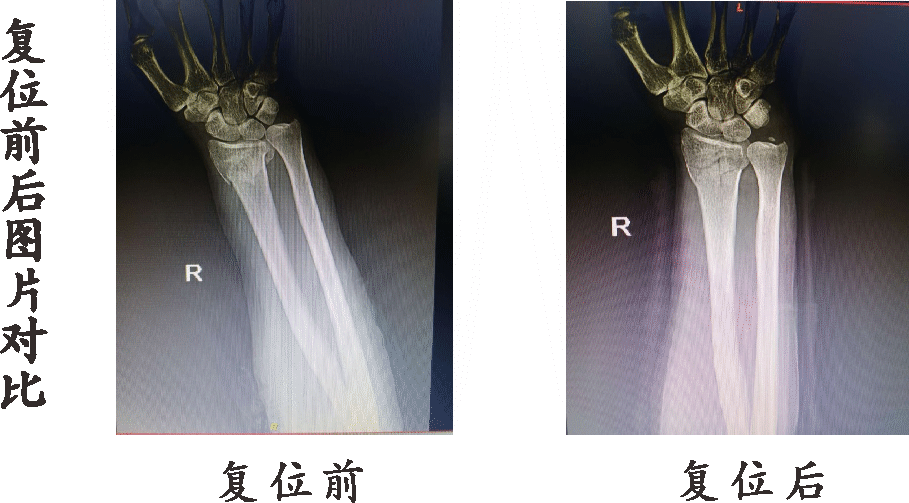

●骨折手法复位

传统手法整复、夹板外固定治疗。手法整复应根据骨折复位“欲合先离,离而复合”的道理,要先使骨折断端充分分离,充分拔伸牵引,解除短缩畸形,恢复骨端长度。再行端提按压手法整复成角或侧方移位。折顶时应根据骨折端移位及成角的大小,适度灵活运用。

骨折手法复位一般采取中医传统的拔伸牵引、提按端挤、折顶回旋等手法,配合复位和小夹板固定,同时早期运用内服及外用中草药(活血止痛汤、骨伤药酒等)及中医非药物治疗,可大大缩短治疗时间,加速康复,同时配合传统中医康复手段(如:云手、太极拳等),可促进早期功能恢复,减少关节僵硬,创伤性关节炎、肩手综合征的发生。